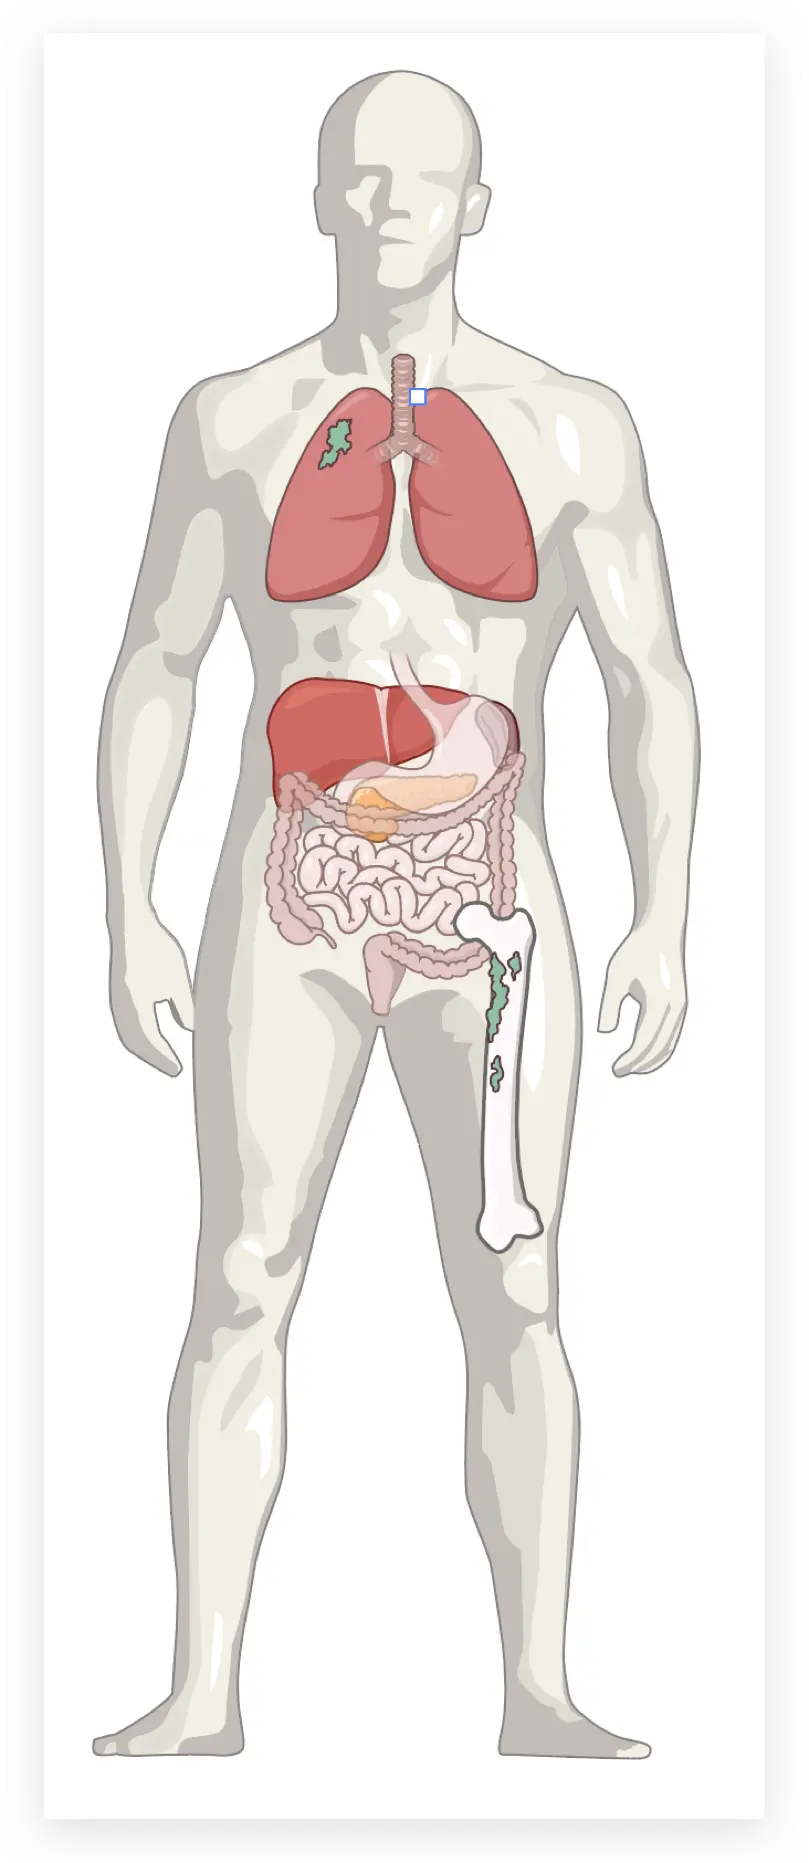

人体部分

钢笔工具勾勒出外轮廓

画出阴影

增加细节

调整透明度

画出肺的外轮廓

上色

加上暗部和绿色区块

肝和胃等也逐一画出

肠子画出

最后是骨头

排版上去

排版一下

完成了